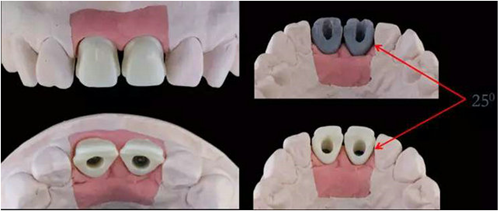

11,21 ASC 全瓷基臺(tái)一體冠蠟型

Asc基臺(tái)數(shù)字化設(shè)計(jì)

螺絲通道改變25°

通過改變螺絲通道角度,調(diào)整螺絲開口位置